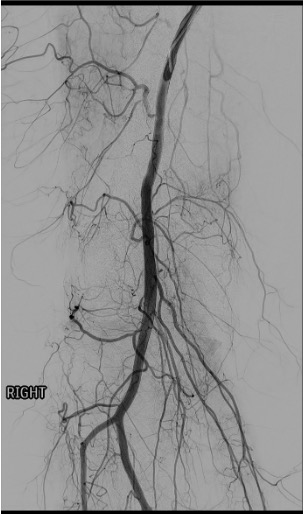

Baseline angiography: SFA and popliteal artery runs in AP and oblique projections to identify all genicular arteries and their branching patterns.

Angiographic hyperemia / synovial blush in the symptomatic territory is the primary target. This appears as a late-phase parenchymal blush beyond the normal capsular stain.

Reassess after each vessel — completion angiogram to confirm treatment of the blush and exclude non-target deposition.

Pre-embolization selective genicular angiogram demonstrating hypertrophied vessels and synovial hypervascularity in the territory of the patient's pain.Post-embolization angiogram showing pruning of the abnormal hypervascularity with preserved flow to normal tissue — the desired endpoint.